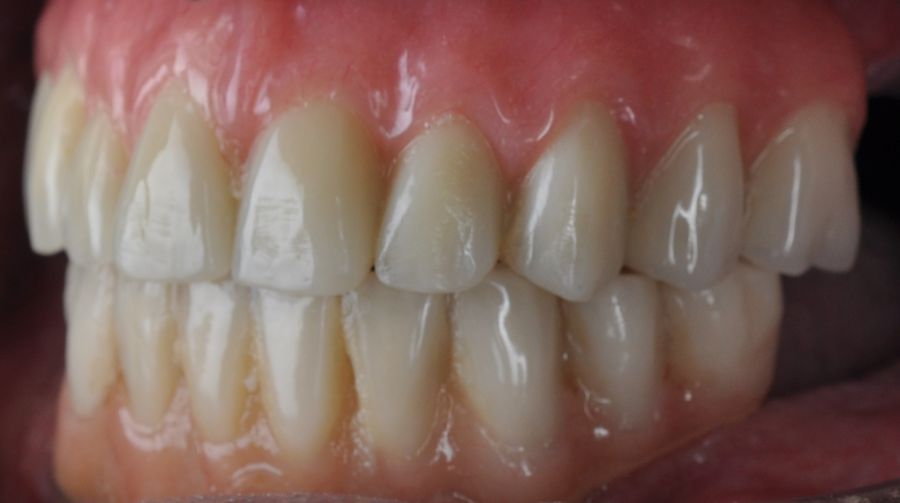

Two months later, with the soft tissues healed around the connections (Figure 16), a new intraoral scanning was made of the implants and the provisional prosthesis for future restoration. A FRI type passivity test (rigid impression splint) was manufactured with an aluminium structure to assess the correct fit on the implants (Figure 17). For implant-supported rehabilitation, a sintered structure was made in chrome-cobalt with machined bases covered with acrylic resin teeth from Bredent® (Figures 18-21).